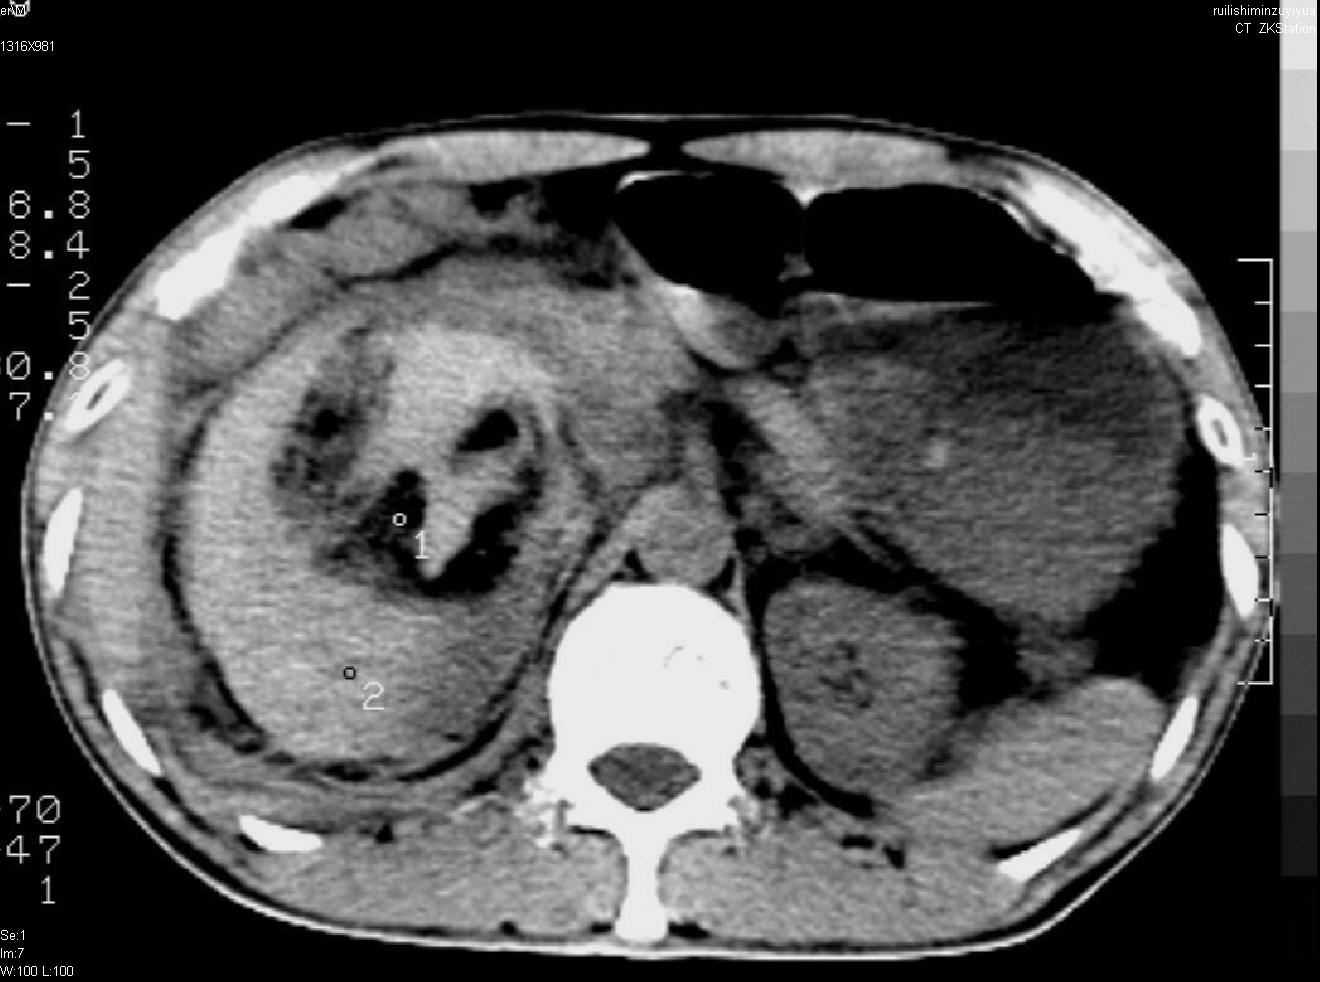

以下是引用liuyue在2007-12-3 6:27:00的发言:[br]右肾区可见密度不均匀、边缘欠清之肿块影,肾脏筋膜增厚,周围脂肪密度增高。右侧胸膜腔内可见少量液体密度影。考虑:1.右肾错构瘤(肾血管平滑肌脂肪瘤)可能性大。2.右侧少量胸腔积液。[br] 鉴别:1.肾脂肪肉瘤。2.肾平滑肌肉瘤。3.肾错构瘤恶变。

以下是引用dyqct在2007-12-3 7:38:00的发言:[br][quote]以下是引用liuyue在2007-12-3 6:27:00的发言:[br]右肾区可见密度不均匀、边缘欠清之肿块影,肾脏筋膜增厚,周围脂肪密度增高。右侧胸膜腔内可见少量液体密度影。考虑:1.右肾错构瘤(肾血管平滑肌脂肪瘤)可能性大。2.右侧少量胸腔积液。[br] 鉴别:1.肾脂肪肉瘤。2.肾平滑肌肉瘤。3.肾错构瘤恶变。